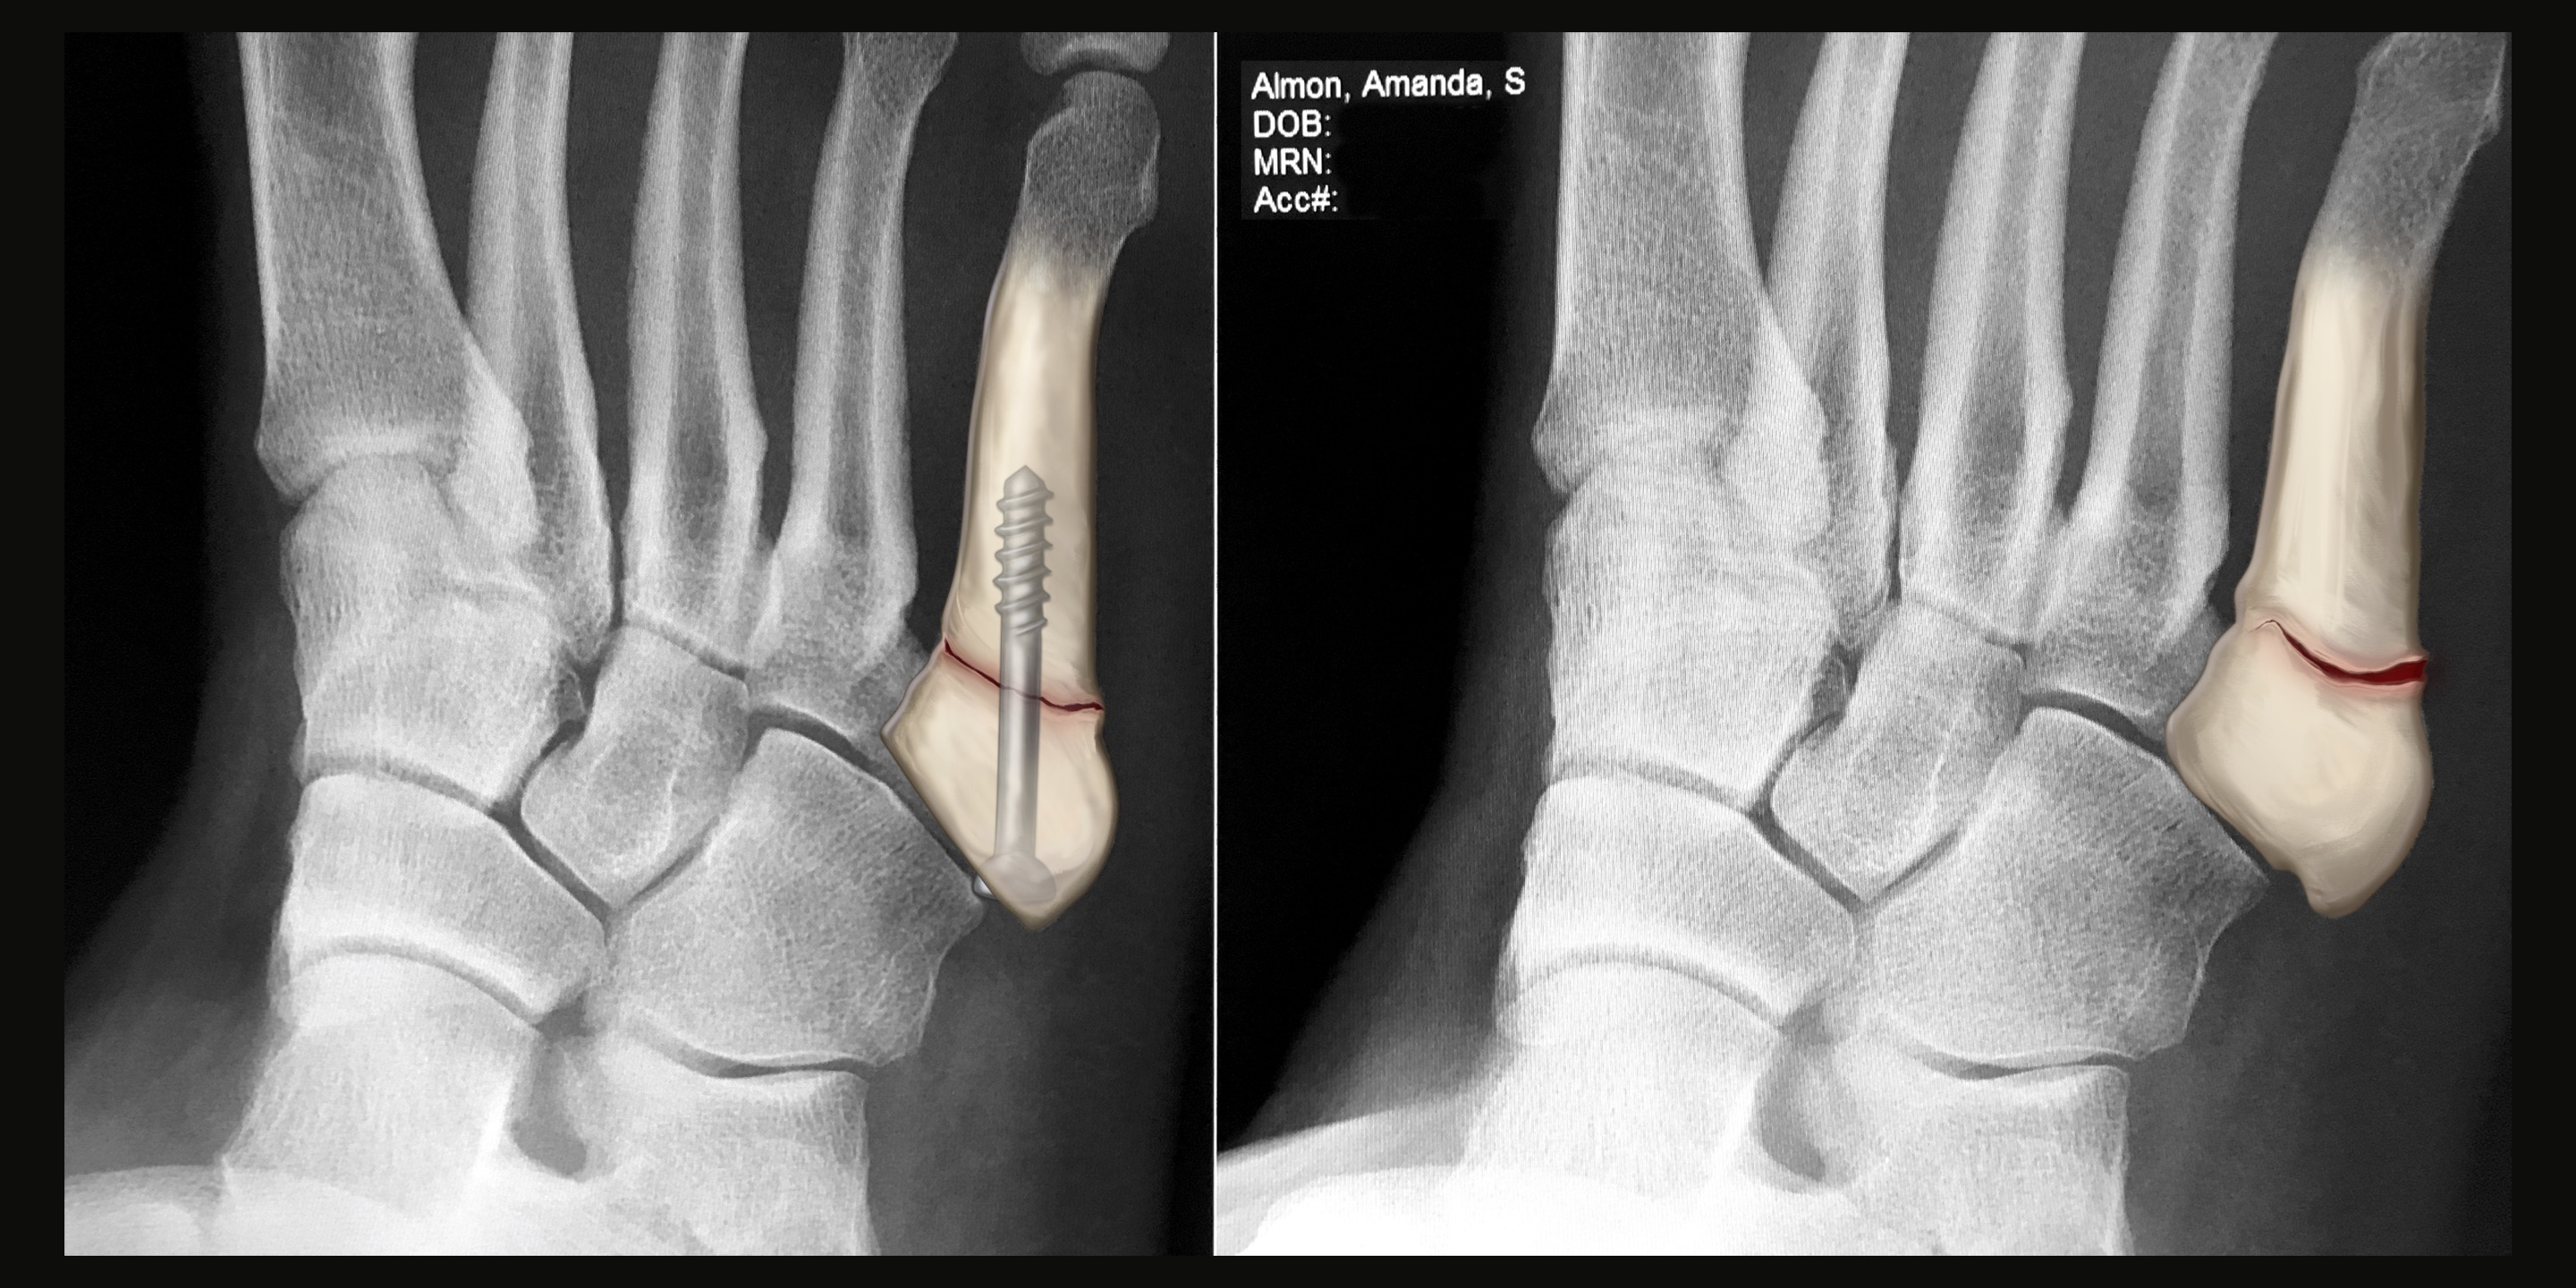

CT scans, MRIs, and X-Rays are all, in a way, portraits of the patient. Films that result from a diagnostic exam display information that is deeply intimate by nature but is often incomprehensible to the patient. The patient learns about themselves and their condition, whether chronic or newly diagnosed, from the words of their physician. Someone without any medical training sees themself as a series of black, white, and gray shapes on a computer screen or printed out on a film. Flesh and bone are abstracted in a way that disconnects them from the body which they represent.

This abstraction and disconnection creates a complicated encounter – how does one relate to an image of themselves when, from their perspective, it looks like little more than television static?

In instances like this where an artist is given a prompt, platform, and permission to create, it is possible to unify select individuals with their films. A patient is elevated to an individual human being by linking a face, name, and snippets of their personality with what would otherwise be a diagnostic assessment reserved for the eyes of physicians. This exhibition is about connecting the individual to themselves and others, and furthering the integration of art and science. Disclosure aims to dignify a patient and their condition through a work of art, and bridge the gap between the results of a diagnostic medical exam and what makes us human.